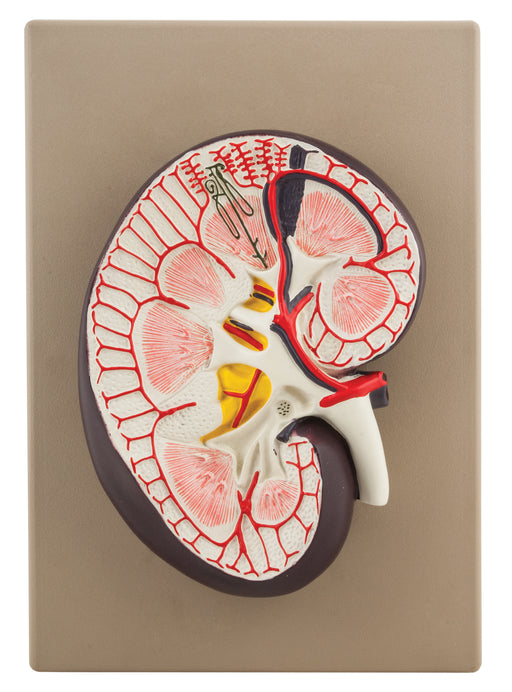

Human Kidney Cross Section Model - 3X Life Size

3x life size (9" X 6.5" X 3") 3D cross section connected to base Detailed Internal Anatomy (cortex, medula, pelvis of ureter, ureter, nephron (Hen...

View full detailsAM0106 -